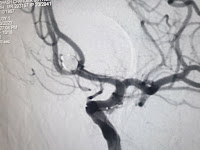

Alchemist Hospital Panchkula with the history of sudden onset of severe headache 15

days prior and then again seven days back. Diagnosis found to be having

ruptured (twice) Acom(anterior communicating artery) Aneurysm. The patient was in a very drowsy condition and general status with weakness in both lower limbs.

Hospital performed the procedure i.e balloon-assisted Coiling known as Endovascular

coiling. It is a minimally invasive technique

used for the treatment of brain aneurysm, which are balloon-like outpouchings of

blood vessels in brain aneurysm, if ruptures, is life threatening. So patient needs

urgent attention and treatment.